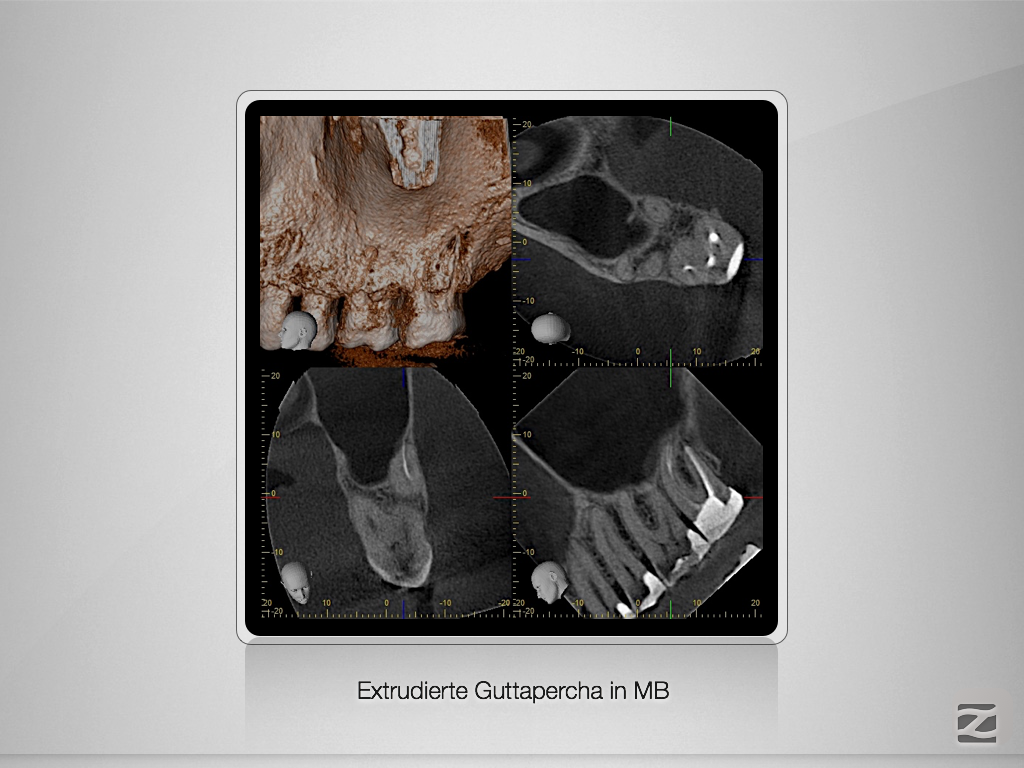

Die gute alte Hedströmfeile